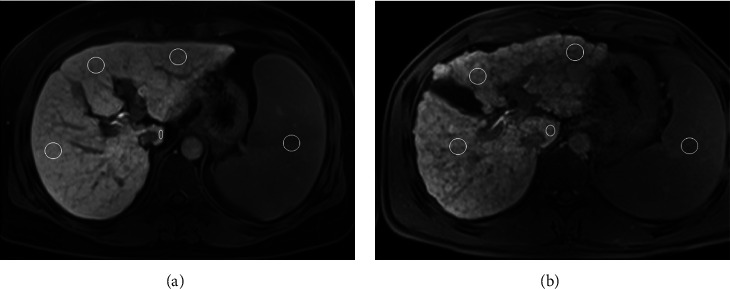

Methods: Forty-four consecutive patients with hepatitis B-related cirrhosis who underwent Gd-EOB-DTPA-enhanced MRI were divided into compensated and decompensated statuses based on clinical evaluation. Volume and signal intensity of individual lobes were retrospectively measured to calculate HUI of the right liver lobe (RHUI), medial (MHUI) and lateral (LHUI) left liver lobes, and caudate lobe (CHUI). Spearman's rank correlation analyses were performed to evaluate relationships of lobe-based HUI with Child-Pugh and model for end-stage liver disease (MELD) scoring system scores in compensated and decompensated statuses. The Mann-Whitney U-test was used to compare the lobe-based HUI between compensated and decompensated statuses. The performance of lobe-based HUI in distinguishing cirrhosis was evaluated using receiver operating characteristic (ROC) analysis, and the area under the ROC curve (AUC) was calculated as a measure of accuracy. Delong's method was used for statistical analysis to elucidate which HUI is optimal.

Abstract Image